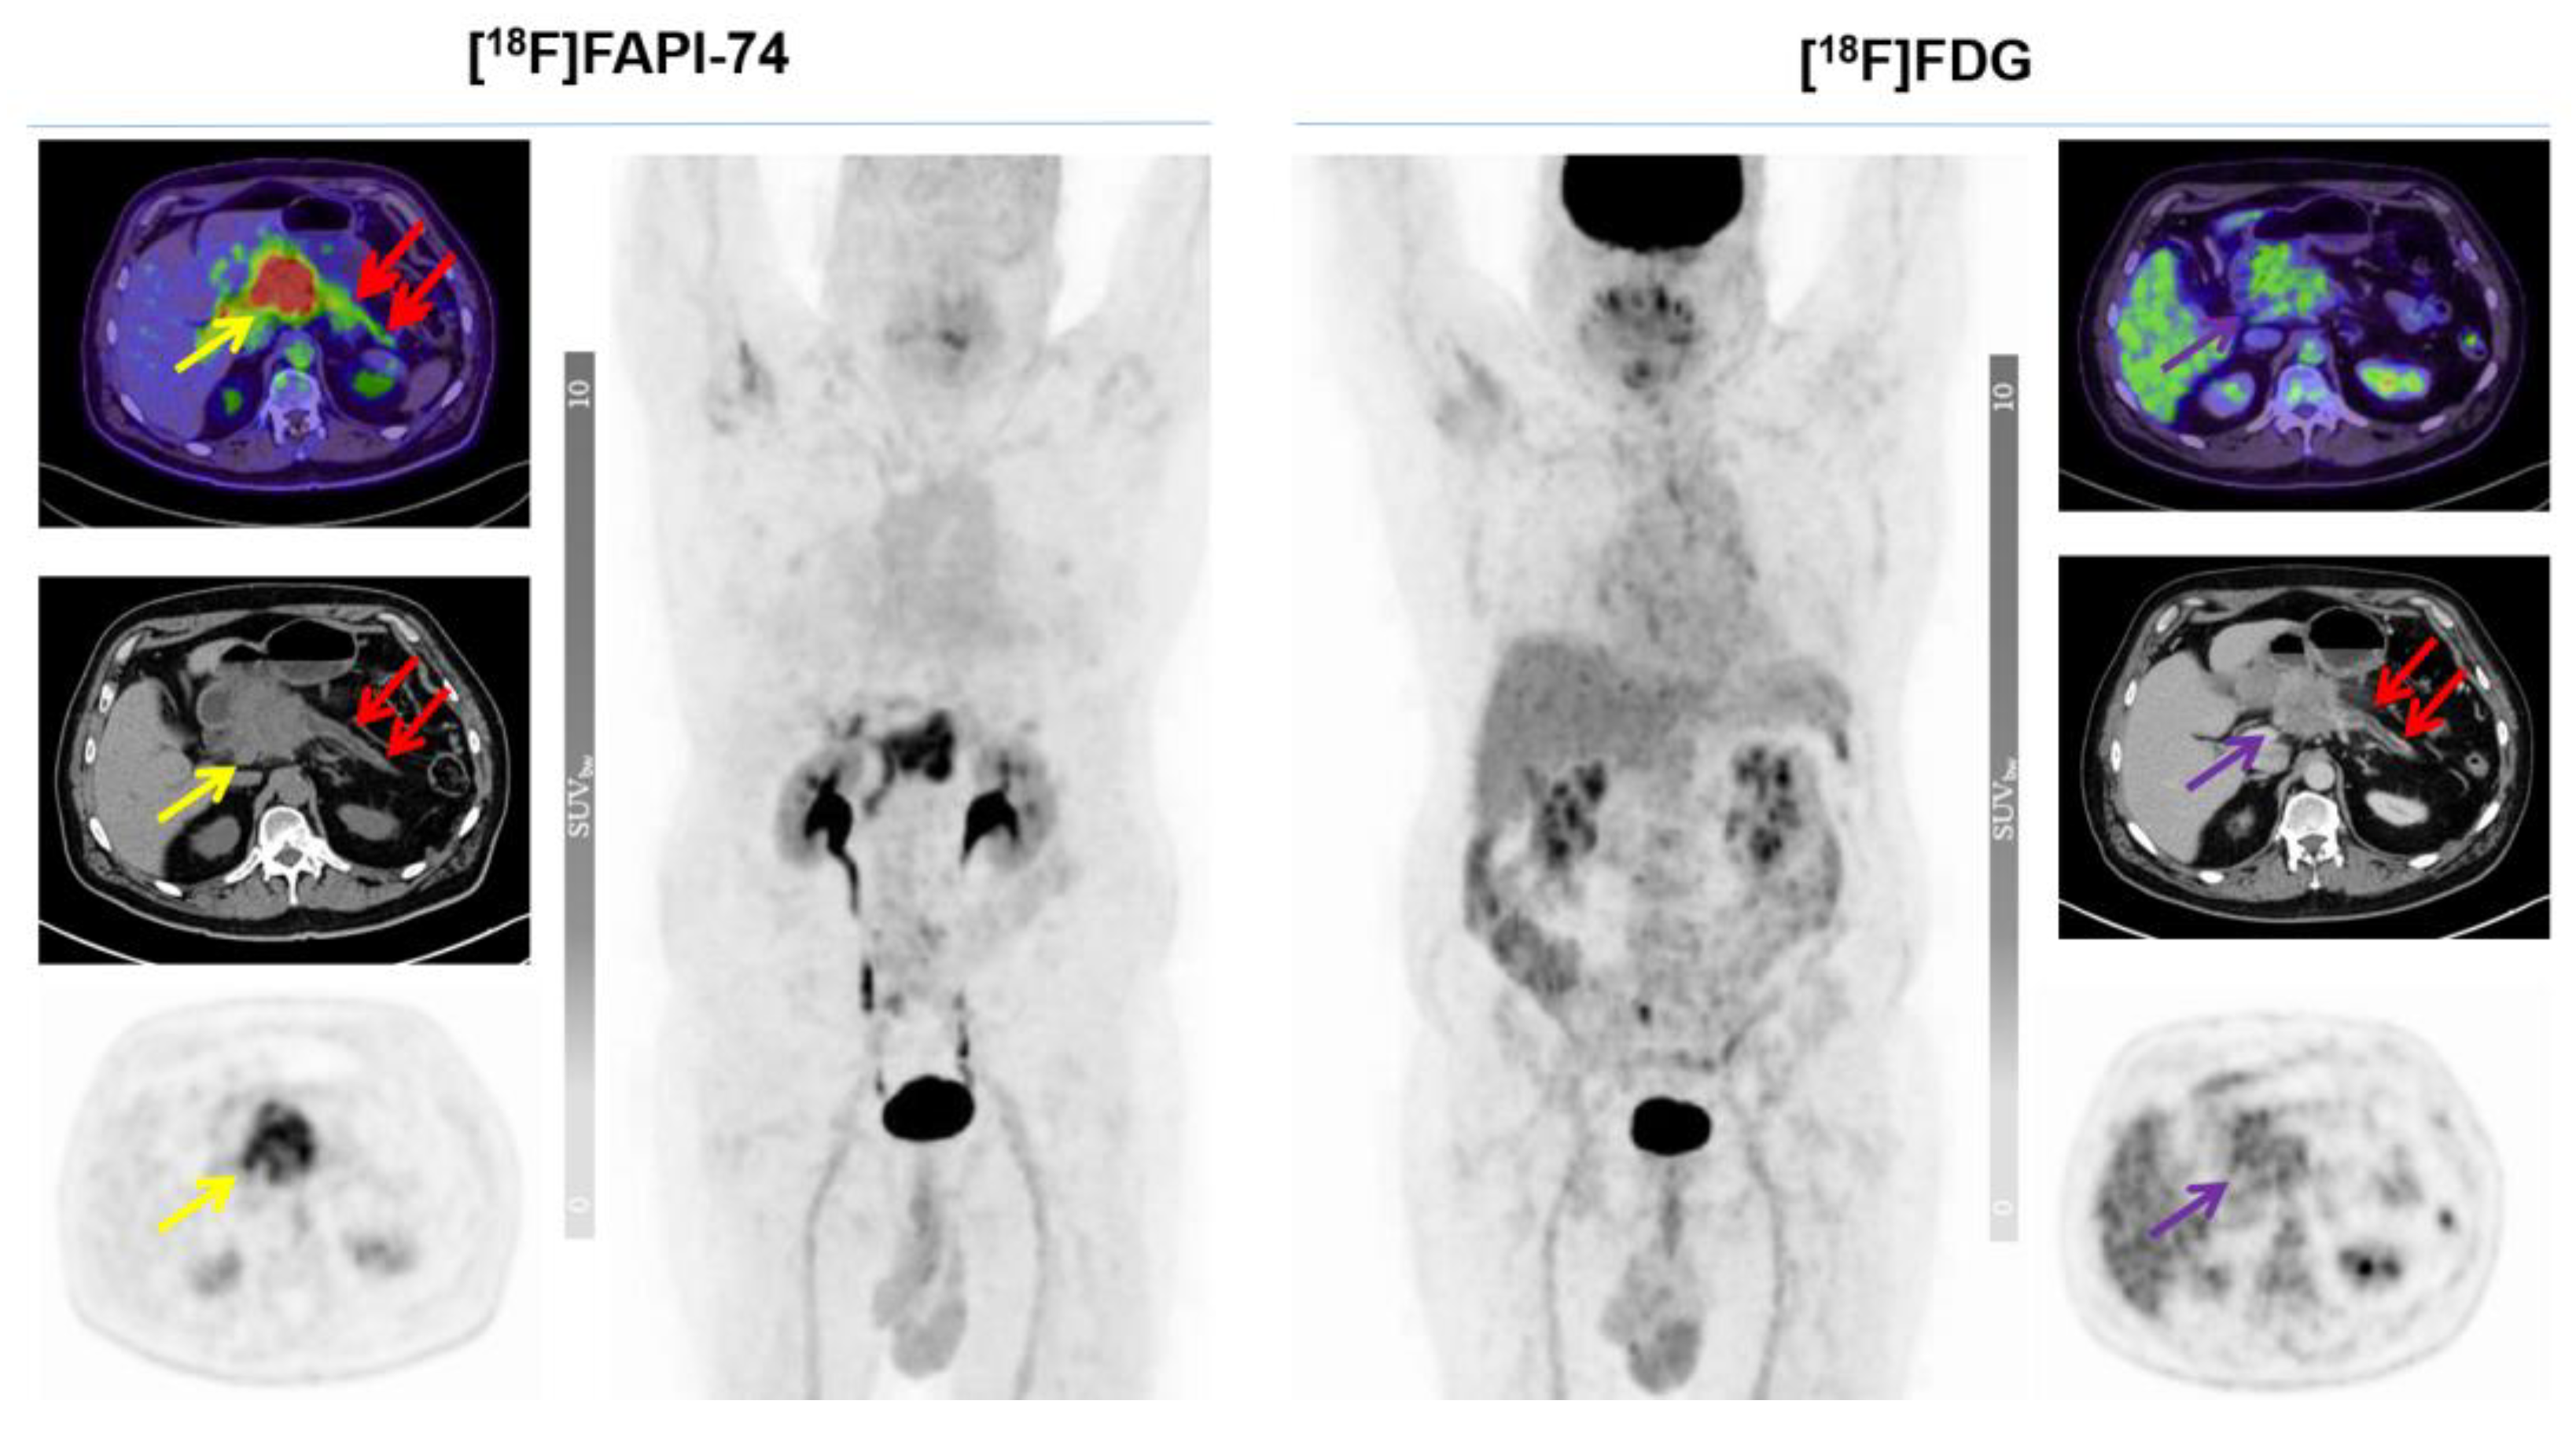

3.4. [18F]FAPI-74 in PDAC with Confounding Pancreatitis